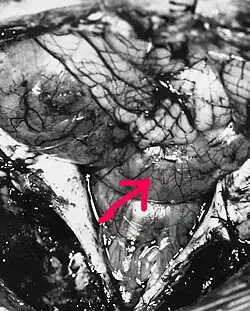

![]() МРТ больного с эпендимомой IV желудочка в Т1-взвешенном режиме. Опухоль отмечена стрелкой | |

В типичных случаях на МРТ эпендимомы видны в виде объёмных образований, которые заполняют, а иногда и полностью тампонируют полость IV желудочка и распространяются в большую затылочную цистерну или боковую цистерну моста. Солидная часть новообразования на Т1-взвешенных томограммах выглядит изо- или даже гипоинтенсивной и гиперинтенсивной на Т2-взвешенных томограммах[24].